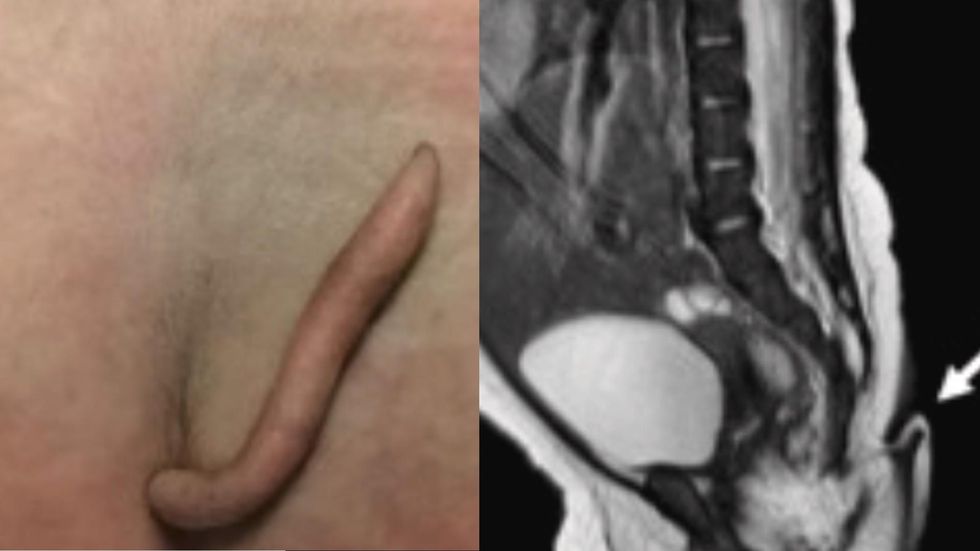

However, there was something quite unique about her - she had a very “rare” 2-inch-long tail that was covered in “fine hair.”

When she received her first examination, doctors discovered the “tail-like structure,” which was around 5.7-centimeters long and was covered with hair.

In another X-ray conducted on the baby, there was no indication of anomalies or bone structures in the tail.

The structure was benign and only had fat and tissue, which is rare as only 40 cases have been documented.

After deeming the tail free of skin lesions, surgeons decided to snip it and reconstruct the area with a Limberg plasty, which is an operation that transplants tissue from a patient’s own posterior.